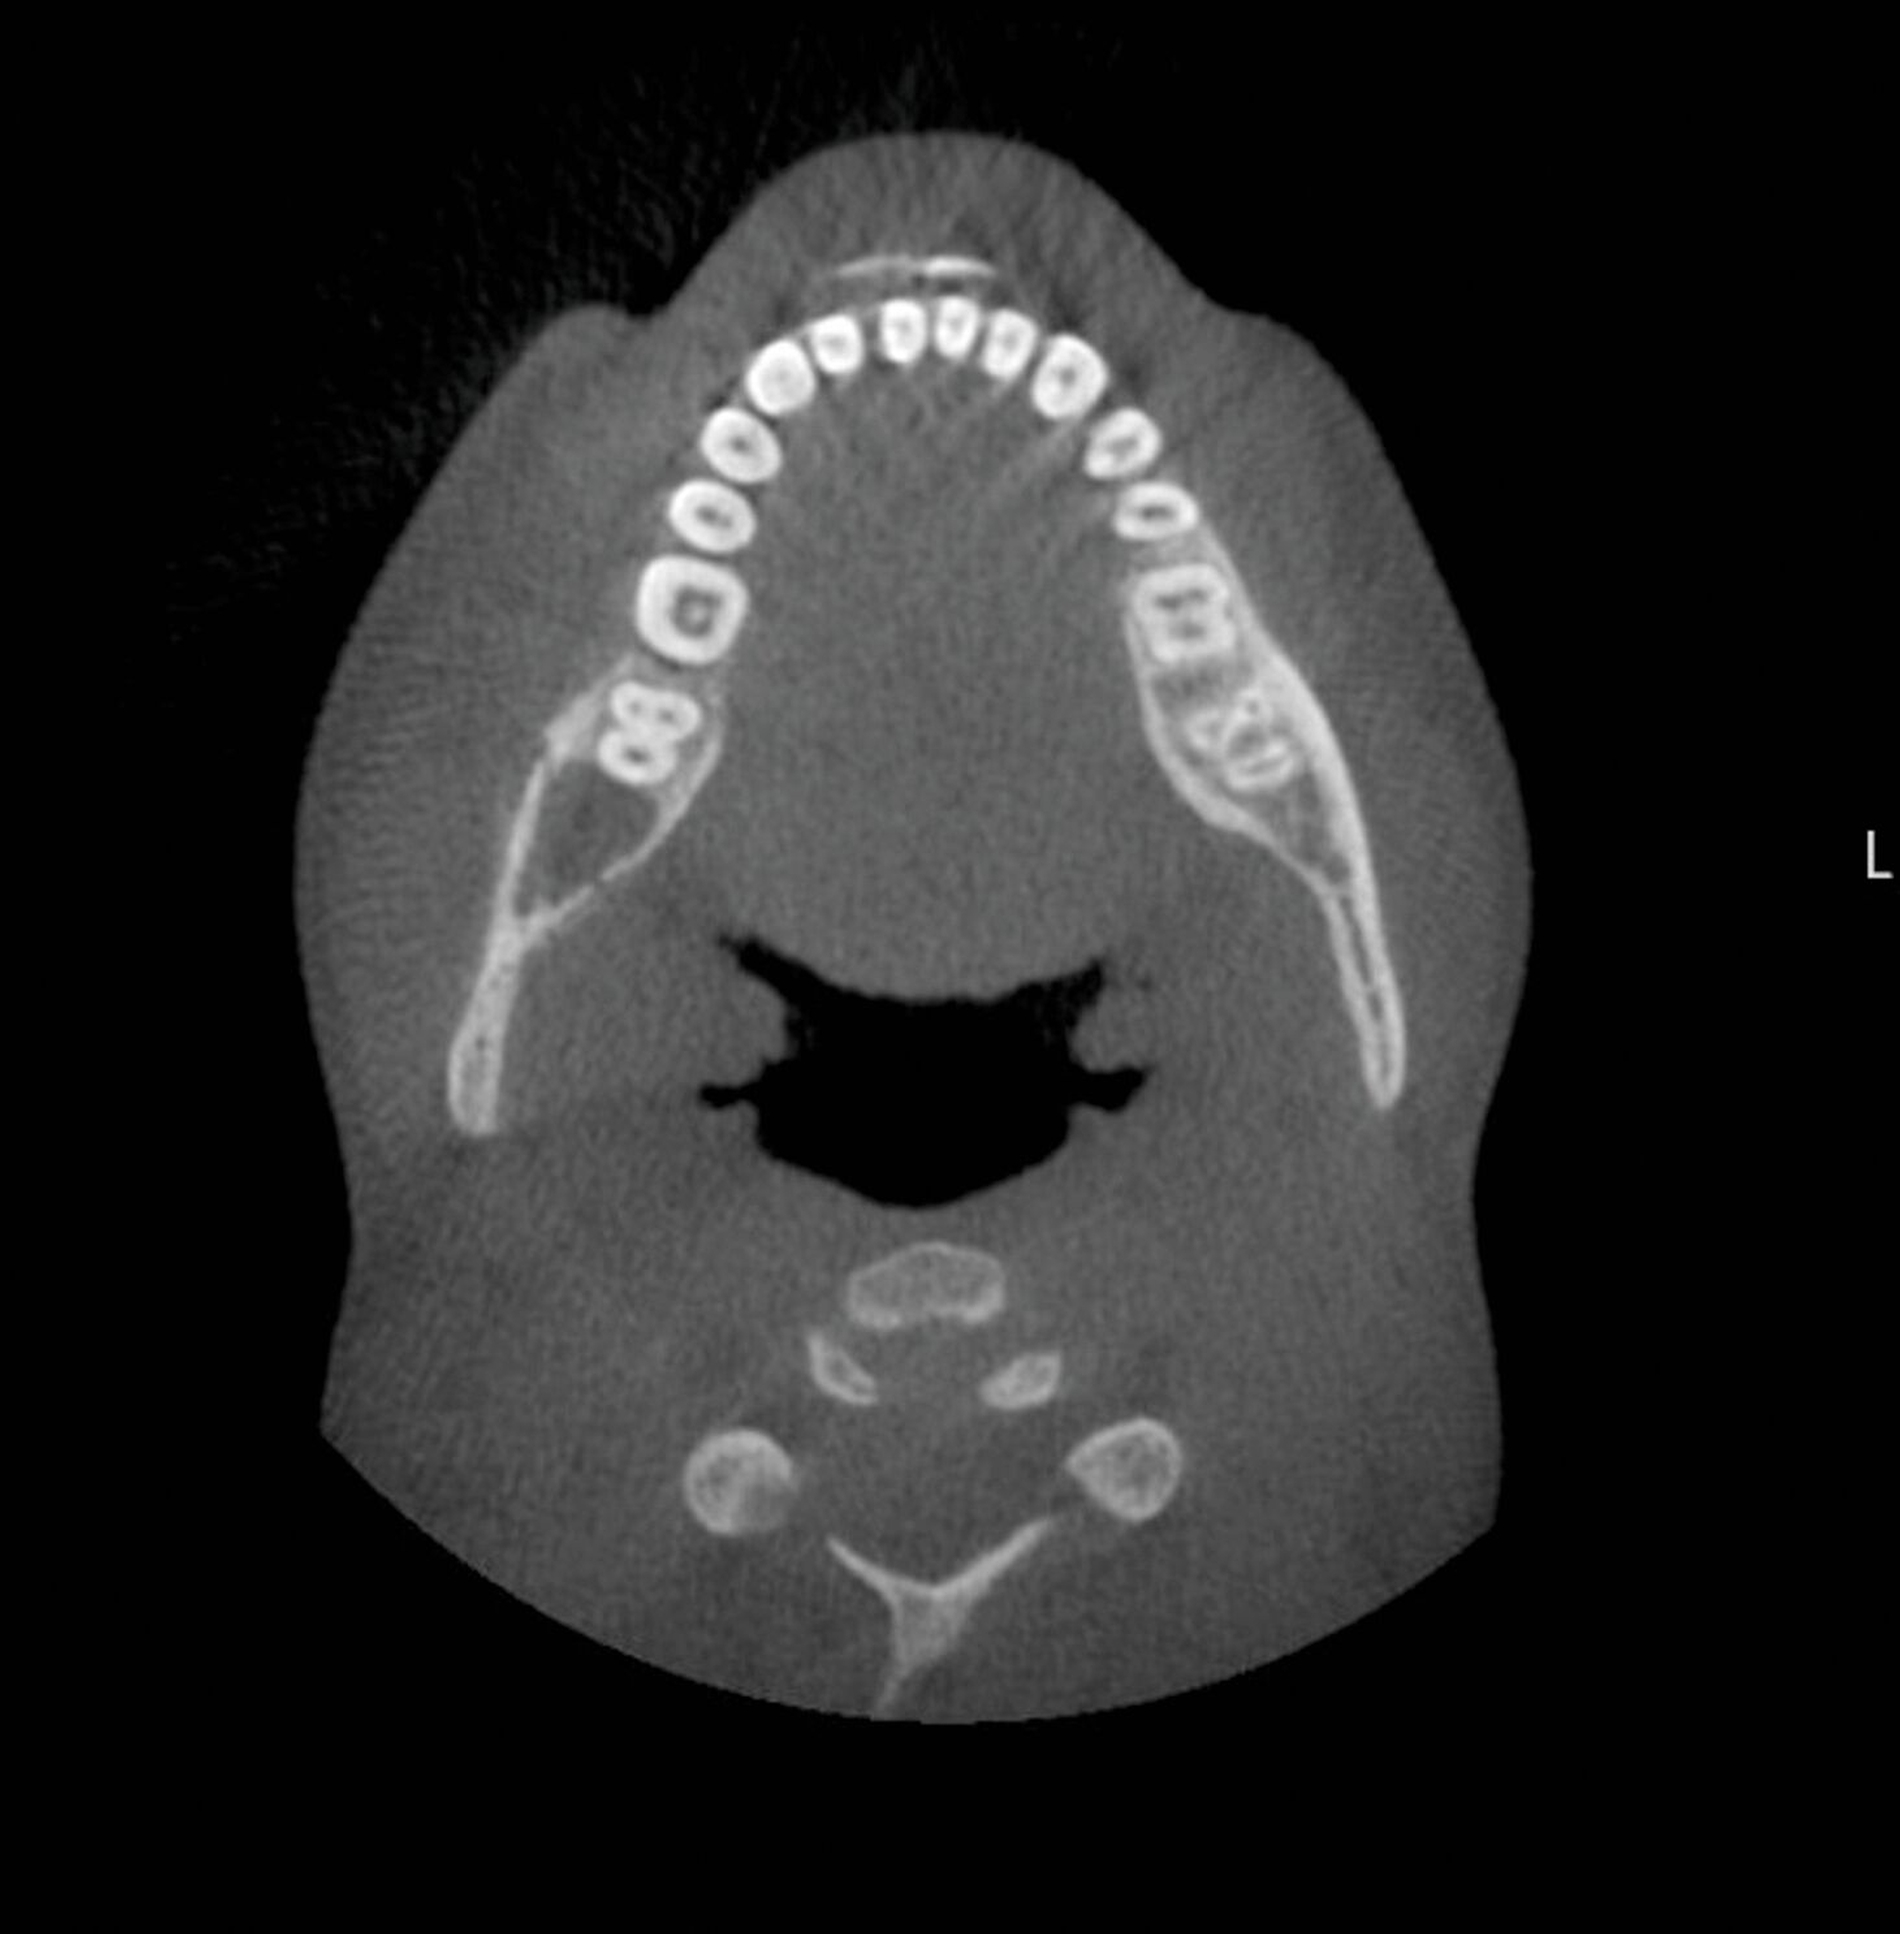

Dieser Patient stellte sich nun mit Schmerzen und Druckdolenz im Kieferwinkel rechts vor. Der enorale Befund zeigte weder eine Fehlokklusion noch ein Os liberum, die faziale Sensomotorik war seitengleich intakt. Die allgemeine Anamnese förderte jedoch eine Osteogenesis imperfecta Typ I zutage („Glasknochenkrankheit“). Das ad domo angefertigte DVT ergab den Befund einer Fraktur an der Linea obliqua rechts (Abbildung 2).